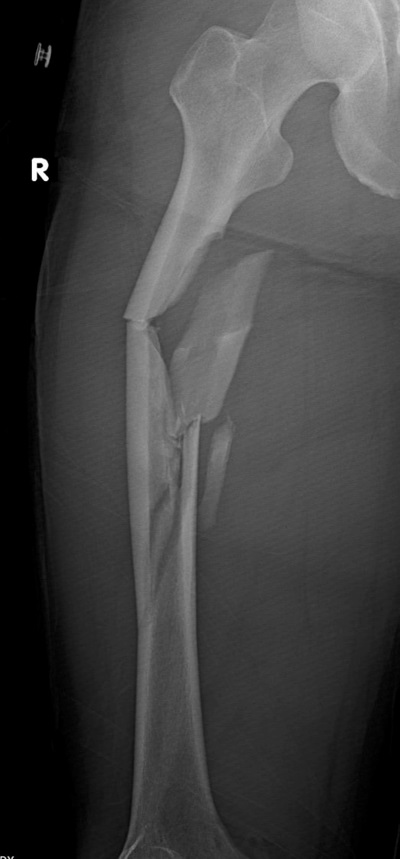

• Femur Shaft Fractures (broken Thighbone) - Orthoinfo - Aaos

Comminuted fracture healing time - prizediki

Source: thumbs.dreamstime.com